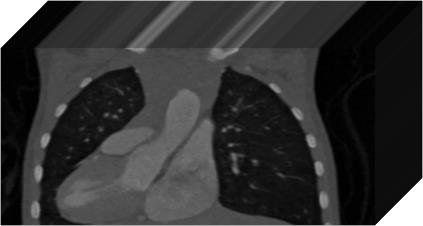

The success of deep learning heavily depends on the availability of large labeled training sets. However, it is hard to get large labeled datasets in medical image domain because of the strict privacy concern and costly labeling efforts. Contrastive learning, an unsupervised learning technique, has been proved powerful in learning image-level representations from unlabeled data. The learned encoder can then be transferred or fine-tuned to improve the performance of downstream tasks with limited labels. A critical step in contrastive learning is the generation of contrastive data pairs, which is relatively simple for natural image classification but quite challenging for medical image segmentation due to the existence of the same tissue or organ across the dataset. As a result, when applied to medical image segmentation, most state-of-the-art contrastive learning frameworks inevitably introduce a lot of false-negative pairs and result in degraded segmentation quality. To address this issue, we propose a novel positional contrastive learning (PCL) framework to generate contrastive data pairs by leveraging the position information in volumetric medical images. Experimental results on CT and MRI datasets demonstrate that the proposed PCL method can substantially improve the segmentation performance compared to existing methods in both semi-supervised setting and transfer learning setting.